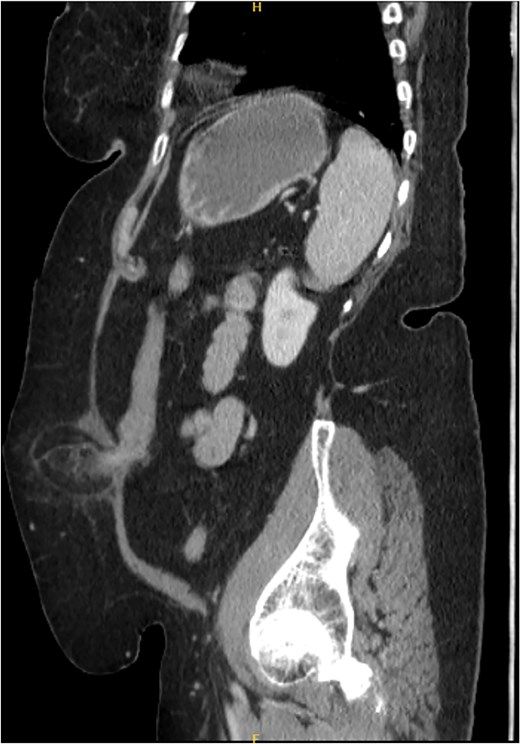

Postoperatively, the patient had an uneventful course and was discharged on Day 5. At the 6-month follow-up, she remained asymptomatic. A CT scan performed at her request for reassurance showed no signs of recurrence or acute abdominal pathology (Figs 4 and 5).

Sagittal section of CT abdomen and pelvis 6 months after the surgery.